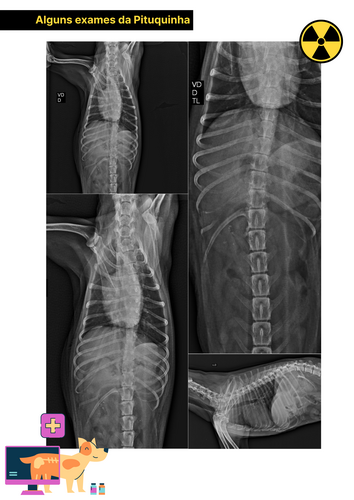

Ajude Pituquinha 🐶